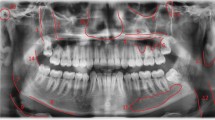

Turner's painting of a dental surgeon's rooms, discussed in the first of these two papers,1 is a very satisfying work of art, successful in its relaying of a domestic drama, and also fulfilling Payne Knight's commission to produce a work to equal that of the older masters. It cannot, though, be relied upon to show us what a late Georgian dentist's rooms actually looked like. For this we are very fortunate to have Turner's sketchbook, with its preparatory drawings for the painting.